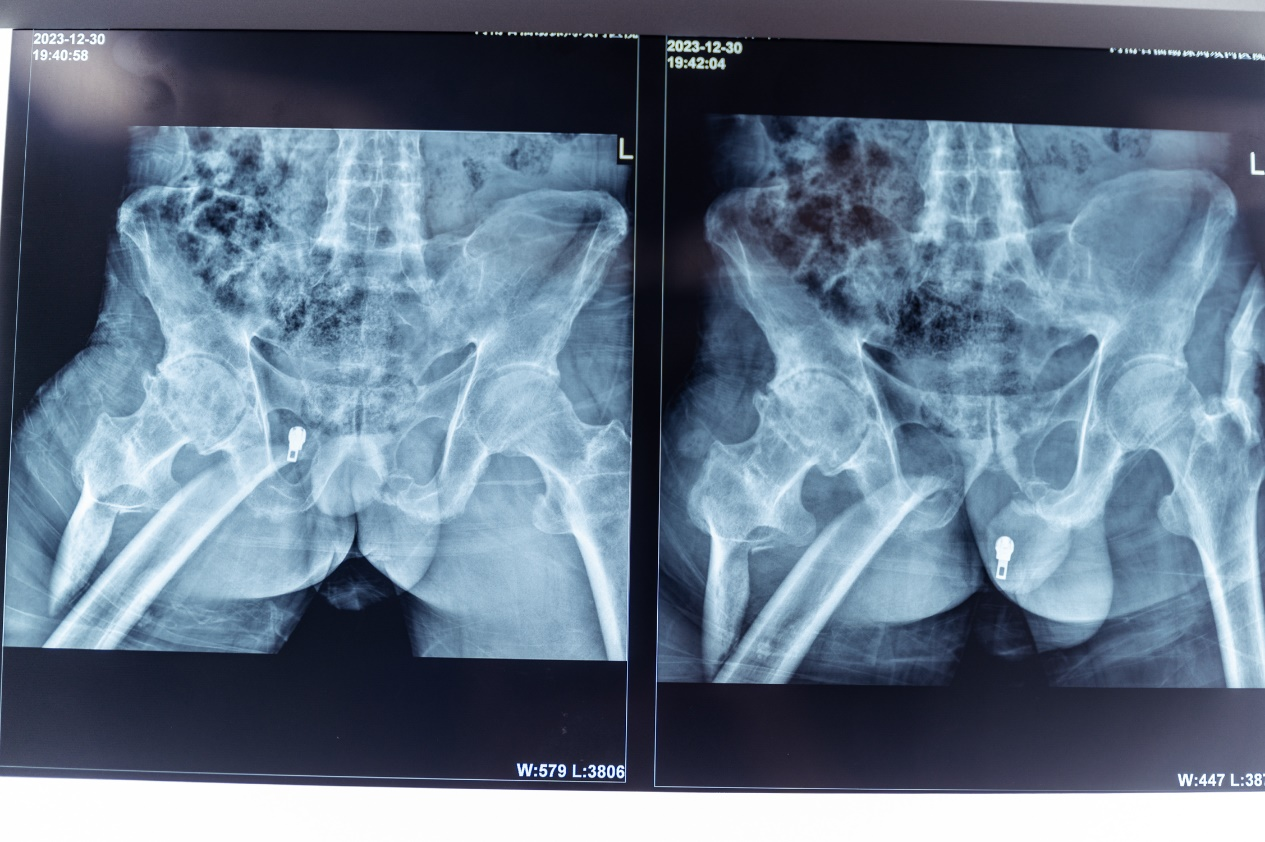

强直性脊柱炎引起髋关节间隙变窄,屈髋畸形,骨折断端移位大,复位困难。

6.调节牵引力与方向,X线透视骨折短缩畸形纠正。

7.牵引下钢丝环扎纠正侧方移位,X线透视解剖复位

9.术后复查X线片,解剖复位,内固定物固定牢固。